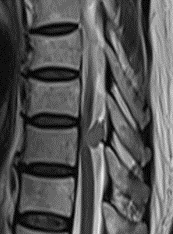

Cirugía para patologías degenerativas: tratamiento para enfermedades del disco intervertebral ya sea cervical, cirugías de la columna cervical por abordaje anterior o posterior. Con o sin fijación con tornillos y abordajes dobles en los casos necesarios (XLIF, OLIF) en pacientes con escoliosis degenerativas. Hernias de disco dorsal ya sean abordajes laterales o posteriores. Hernia de disco lumbares o estenosis foraminales por técnicas de mínima invasión.

Las técnicas de mínima invasión ofrecen varias ventajas: incisiones pequeñas, menor riesgo de complicaciones, menor sangrado, menor agresión a los tejidos, rápida movilización y recuperación del paciente, generalmente el paciente puede ser dado de alta al día siguiente.